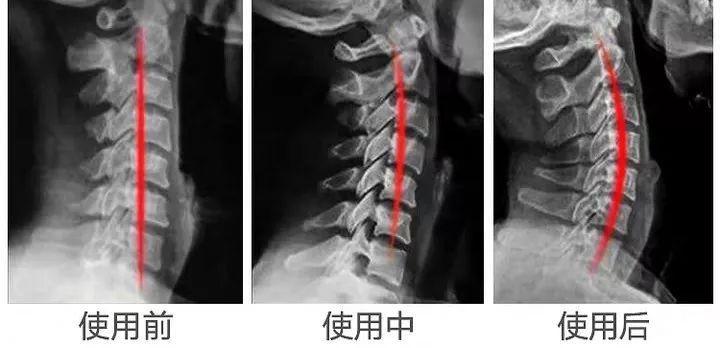

人正常的颈椎是有弧度的,大约是前凸30°-45°。

但随着颈椎长时间承受巨大压力,过于疲劳的状态。于是,弧度就逐渐退化变直,甚至反弓。

前凸的颈椎曲度被改变,结果就是引发椎间盘突出,造成对血管和神经的压迫,容易出现颈椎僵硬、头晕、头痛的症状。

就这样,每天睡前牵引30分钟,就能让颈椎就慢慢恢复到正常曲度。

每天睡前30分钟,长期使用,告别肩颈疼痛,恢复正常生理曲线。